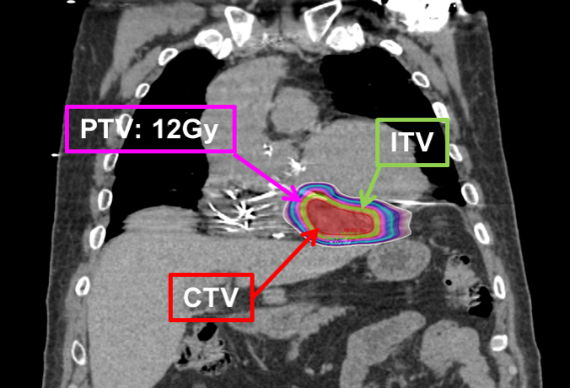

心臟血管醫學中心與放射腫瘤科透過低劑量立體放射手術12格雷,合併3D立體堆疊放射技術,做為抑制心臟不正常放電神經迴路區,達到療效並保護心臟功能之最低潛力劑量。與25格雷放射手術比較,可成功降低心臟內的輻射劑量達58-98%,降低副作用發生的風險,但後續仍需更多案例與研究確立因果關係。